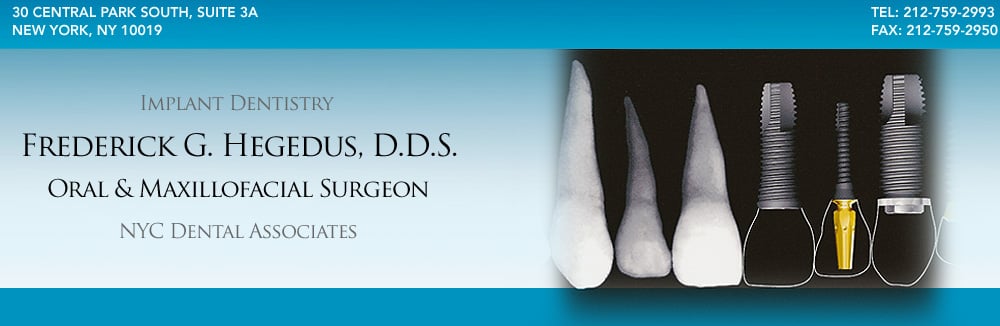

There are two upper (maxillary) and two lower (mandibular) eyeteeth (canine or cuspid). Canine teeth have the longest roots of any human teeth, thus have an especially firm connection to the jawbone. They usually come into place (erupt) around age 13.

An impacted tooth essentially means that it is blocked, stuck, or unable to fully erupt and function properly. The upper canine teeth are the second most common teeth after third molars (wisdom teeth) to become impacted. Impacted canines require surgical treatment (exposure) to enable them to erupt.

Closing gaps: Canines are the last of the front teeth to erupt and therefore close any unsightly gaps between the other front teeth.

Proper alignment and function: Canine teeth are essential to the correct alignment and function of the other teeth on the dental arch. Missing or impacted canines can greatly effect the function of the teeth and the esthetic appearance of the smile.